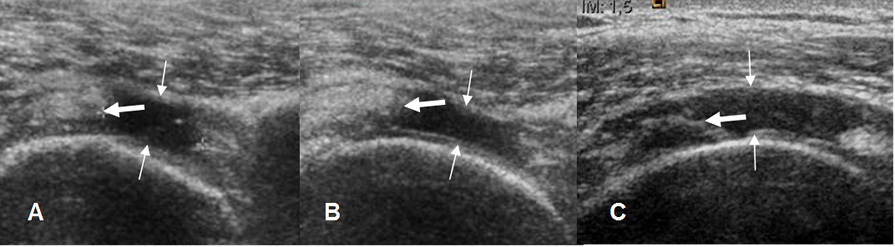

Fig 108. Ruptura del supraespinoso.

A, B y C: Ecografía coronal. Solución de continuidad de espesor completo en el tendón del supraespinoso, que está ocupada por líquido, secundario a ruptura completa. Extremo del tendón retraído. (Flecha gruesa).